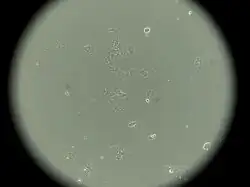

MCF-7 cells have the following characteristics:[2][5][6][7][8][9]

- Primary tumor (invasive breast ductal carcinoma)

- Originate from pleural effusion

- Luminal epithelial phenotype

This cell line retained several characteristics of differentiated mammary epithelium, including the ability to process estradiol via cytoplasmic estrogen receptors and the capability of forming domes.